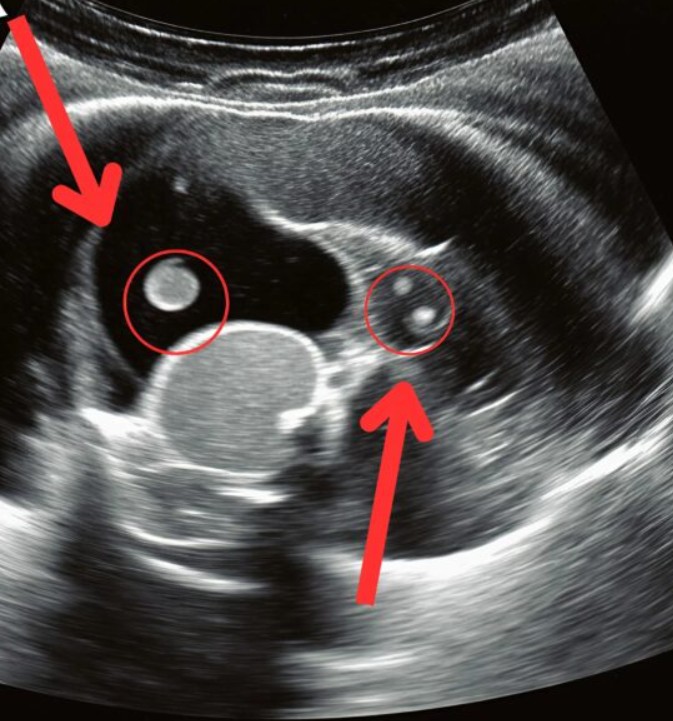

Dans les couloirs de l’urgence, le temps semblait s’être figé. Ma fille se tordait de douleur sur la civière tandis que nous attendions, angoissés, les résultats de l’échographie. Finalement, le médecin est venu vers nous et a prononcé la phrase que nul parent ne veut entendre : « Une opération urgente est nécessaire. » Ce que nous avions pris pour de simples maux de dos était en réalité dû à un calcul rénal silencieux qui s’était progressivement formé. Le calcul s’était déplacé dans le canal, provoquant une douleur intense et un risque vital.